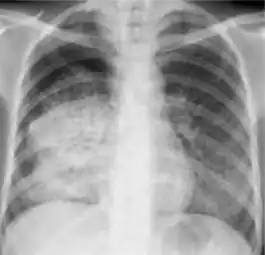

4. Pleural effusion - Presence of a significant amount of fluid within the pleural space. This finding must be distinguished from blunting of the costophrenic angle, which may or may not represent a small amount of fluid within the pleural space (except in children when even minor blunting must be considered a finding that can suggest active TB).

Chest X-ray findings that can suggest inactive TB

This category includes findings that are suggestive of prior TB, that is inactive. Assessments of the activity of TB cannot be made accurately on the basis of a single radiograph alone. If there is any question of active TB, sputum smears must be obtained. Therefore, any applicant might have findings grouped in this category, but still have active TB as suggested by the presence of signs or symptoms of TB, or sputum smears positive for AFB.[2]

The main chest X-ray findings that can suggest inactive TB are:[2]